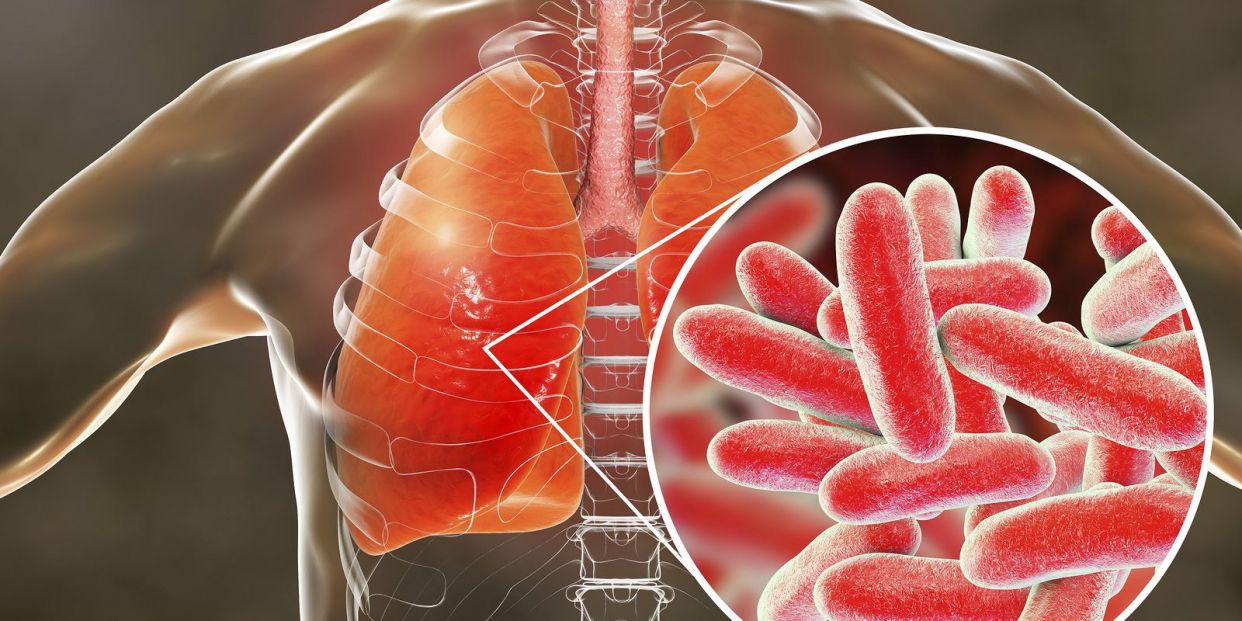

Фотографии бактерий, вызывающих бактериальные пневмонии у животных

Раздел: Другие животные